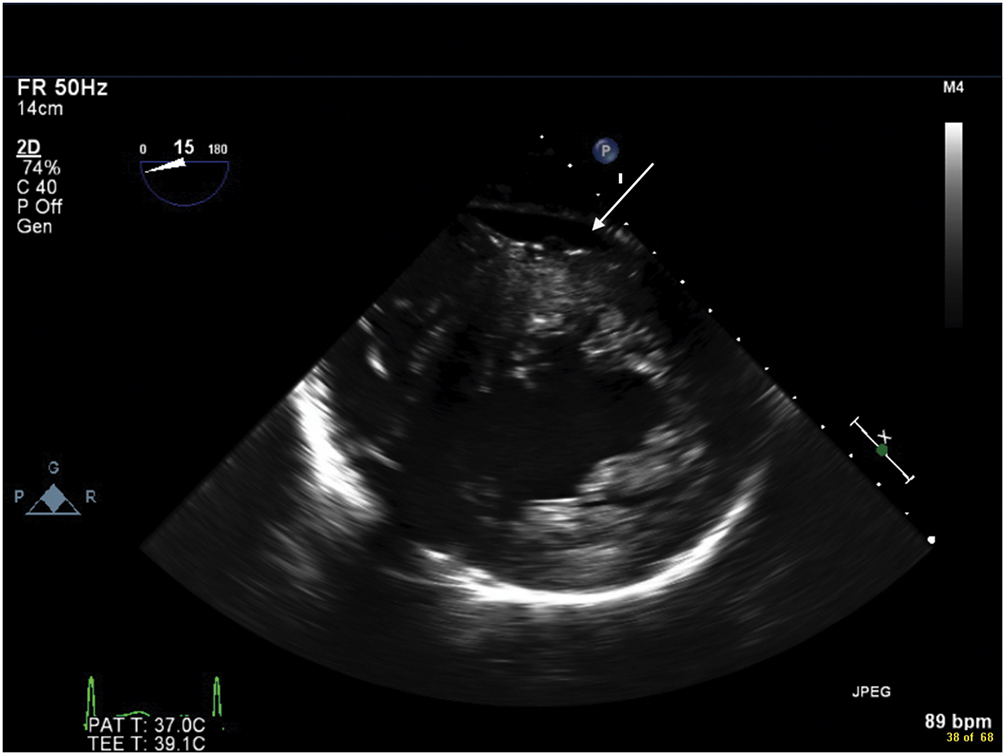

Figure 9.7.: Transgastric Midpapillary View on Transesophageal Echocardiography Demonstrating Accumulation of Blood in the Posterior Pericardial Space (Arrow) after Acute Aortic Dissection.

Transgastric midpapillary view on transesophageal echocardiography demonstrating accumulation of blood in the posterior pericardial space (arrow) after acute aortic dissection.